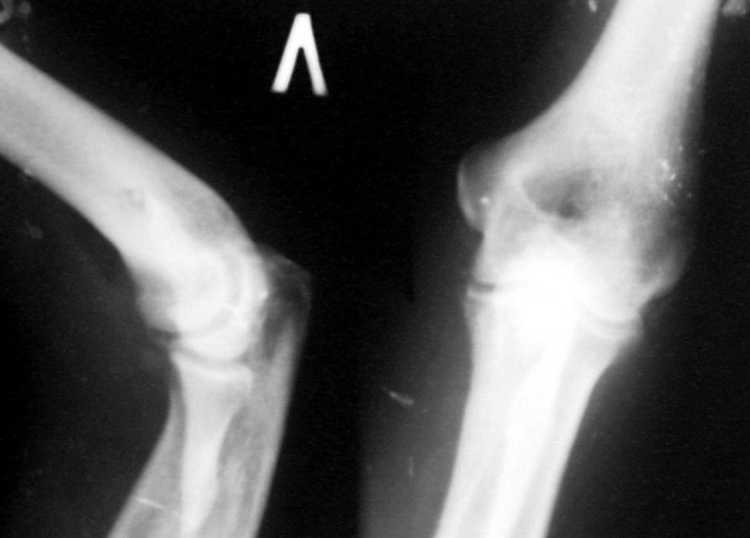

Поступил пациент, 47 лет. травма 15 сентября - вывих предплечья, репозиция. Фиксация 1 месяц. До настоящего времени не обращался. Вот рентенограммы на 2-й и 3-й месяцы после травмы. Неврологии нет. Имеется контрактура локтевого сустава (сгибиние 90, разгибание 120). На снимках что-то похожее на гетеротопические оссификаты, такое впечатление. Как лучше восстановить функцию, возможно ли применить редрессацию? Все-таки локтевой сустав "капризный".С ув. Sergey Melashenko, г. Запорожье

Для суждения о гетеротопических оссификациях нужны снимки хорошего качества, а не то, что есть. Или преобразуйте их в photoshop.

Dear colleguaes! I almost sure this elbow after dislocation and clouse readuction treatment.Despite pure quality of x-ray picture

I suspect small detachment fragment from coronal process.He is lucky guy that haven't instability.

In other side stiff elbow isn't happy prise in the life. In this case I would like to go to open arthrorisis(Column operation ) release anterior joint capsula and after that if you achieve range of movment good on the operation table can use physiotherapy-active assistance exersise and Univerasal elbow brace fixation. If you have not acceptable movement in the operation ( I mean in this case flexion extension 70-150 wiil be good)